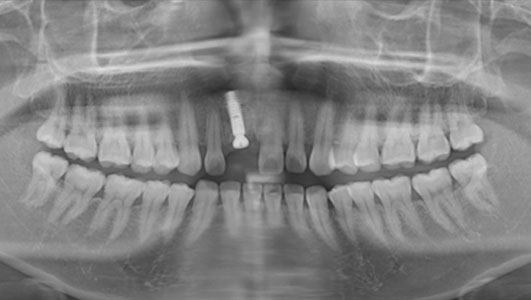

植入种植体之后的X光片

在修复过程中,种植医生首先对汪小姐左上颌缺失牙残留的牙根作了清除,然后在患者牙槽脊上切开少许牙龈,用专用的种牙机,在缺牙部位植进人工牙根,并戴上一颗逼真的临时牙冠,很快一口美观、色泽与功能都与真牙相似的牙齿呈现出来。手术持续约1小时。术后,汪小姐休息片刻就返回办公室工作,即拔即种修复技术帮她重拾了自信。